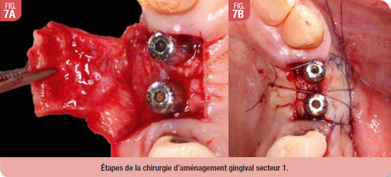

Préparation gingivale

Après une période de cicatrisation de 6 mois, nous procédons au désenfouissement des implants avec un aménagement gingival par lambeau déplacé sans greffe de gencive pour les deux secteurs. Les étapes de l’intervention sont (Fig. 6, Fig. 7) :

- anesthésie locale avec articaïne adrénalinée à 1/100000eme,

- désinfection endo et exo-buccale à la bétadine,

- incisions décalées en palatin avec décharges mésiale et distale,

- lambeau d’épaisseur mixte, désenfouissement des implants et mise en place des vis de cicatrisation,

- fermeture du site avec suture en monocryl 5.0, hémostase et conseils post-opératoires.

La patiente est revue à 15 jours post-opératoires pour contrôle et dépose des points. La cicatrisation est normale (Fig. 8).